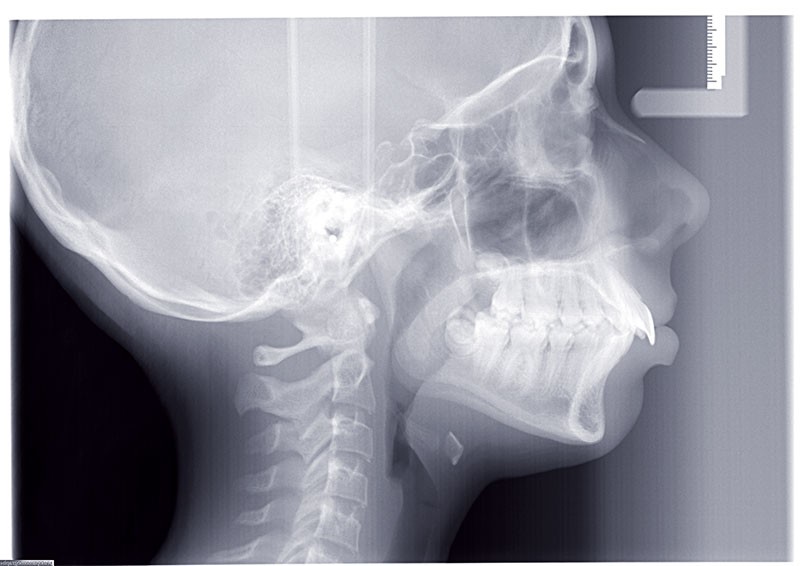

Nous sommes en présence d’une patiente adolescente âgée de 12 ans ½ dans une phase de croissance faciale favorable.

Elle présente une classe II squelettique par rétrognathie mandibulaire et une classe II dentaire molaire et canine droite et gauche associée à une biproalvéolie incisive maxillaire et mandibulaire.

L’environnement vertical est normodivergent.

Le contexte facial est délicat avec un profil cis-frontal, un angle naso-labial très ouvert et un sillon labio mentonnier marqué avec retour de la lèvre inférieure en arrière des incisives maxillaires.

Le pronostic de correction de la classe II est favorable mais il est très important de souligner la vestibuloversion incisive mandibulaire et le risque parodontal associé (fig. 1 à 3).